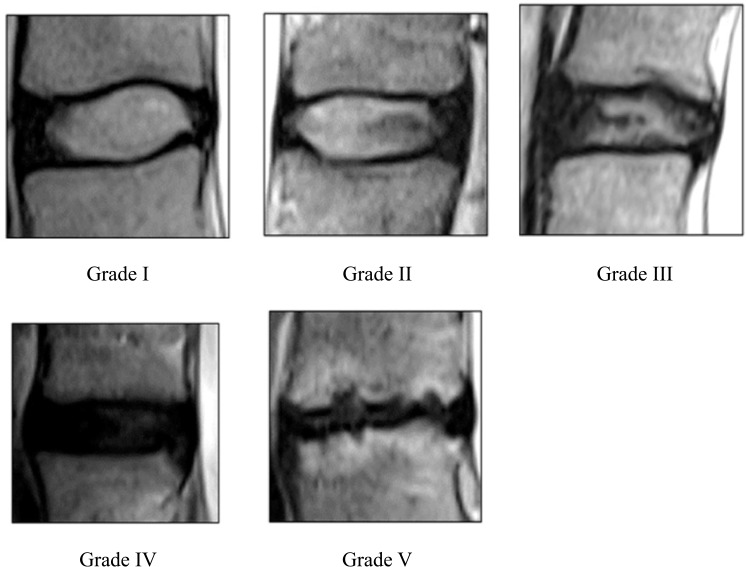

Objectives: This study investigates the relationship between lumbar disc degeneration and sociodemographic factors in a Malaysian cohort, focusing on the diagnostic potential of the disc-cerebrospinal fluid signal ratio (DCFR). With lumbar disc degeneration being a significant cause of low back pain, there is a need for simple yet effective diagnostic measures that are adaptable to diverse imaging conditions. Materials and methods: A retrospective analysis was conducted on 182 patients presenting with low back pain. Magnetic resonance imaging (MRI) was used to assess disc degeneration using the Pfirrmann grading system, while the DCFR was calculated to quantify the severity of disc degeneration. Sociodemographic factors such as age, gender, and race were analyzed for their correlation with degeneration severity and DCFR. Results: The DCFR showed a strong negative correlation with Pfirrmann grades, with older patients and males exhibiting more severe degeneration. Sociodemographic factors significantly influenced degeneration patterns, particularly in the older age groups, with Malays showing a higher prevalence of moderate to severe degeneration. Conclusion: The DCFR provides a consistent and practical quantitative assessment of lumbar disc degeneration. It correlates well with traditional qualitative grading systems and is effective across various age group, making it a valuable tool for clinical and diagnostic applications in diverse populations.